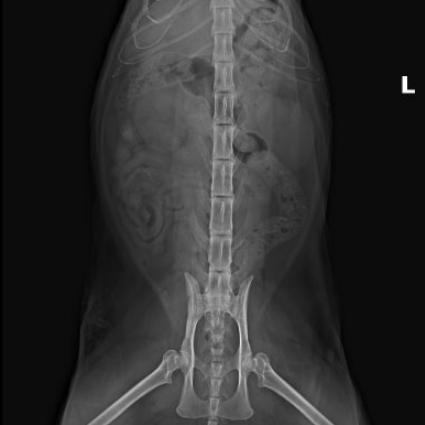

DR检查↓↓

Dr显示膀胱区域高密度影像,膀胱结石。

猫咪尿血来医院检查发现膀胱结石,当天安排了手术,手术前后影像对比,手术将结石全部取出↓↓